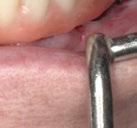

Ejecución técnica quirúrgica mediante férula guiada Bajo anestesia infiltrativa realizamos extracciones atraumáticas de todas las piezas a excepción de los dientes que actúan como anclaje o pilares para la fijación de la férula quirúrgica (Figuras 20 y 21). Seguidamente insertamos la férula comprobando una buena adaptabilidad y estabilidad

(Figuras 22 y 23). Se realiza fresado transgingival mínimamente invasivo y guiado hasta la inserción de los implantes, siguiendo el protocolo preestablecido e indicado (Figuras 24 a 26).

ISQ favorables en la mayoría de los implantes. Seguidamente se extraen los dientes remanentes que han actuado de medio retentivo para la férula quirúrgica.

Dentro de la fase quirúrgica propiamente dicha, una vez terminada la inserción de los implantes y

comprobada su estabilidad primaria, colocamos pilares transepiteliales

Multiplus para registrar una impresión digital mediante escaneado sobre ellos (Figuras 27 a 29)